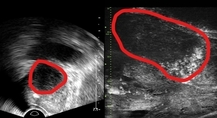

MRI를 찍었을 때 나타날 수 있는 턱관절 이상을 선별하는 AI 모델이 개발됐다.MRI가 필요한 환자를 빠르게 가려내 진단 효율을 높일 수 있을 것으로 기대된다. 연세대학교 치과대학병원 구강내과 박연정 교수와 연세대학교 치과대학 구강과학연구소 정효정 교수, 연세대학교 인공지능융합대학 황성재 교수, 인공지능융합대학원 석사과정 주다윤 연구원 등은 파노라마 X-ray 영상과 임상 정보를 함께 분석해 턱관절 MRI에서 확인되는 이상 여부를 미리 선별하는 AI 모델을 개발했다고 19일 밝혔다. 연구 결과는 국제학술지 ‘npj 디지털 메디신(npj Digital Medicine, IF 15.1)’에 게재됐다. 턱관절 질환은 음식을 씹거나 말을 할 때 사용하는 턱관절 기능에 영향을 미치는 대표적인 구강악안면 질환이다. 턱관절 통증이나 입이 잘 벌어지지 않는 증상, 관절에서 나는 소리 등으로 병원을 찾는 환자가 많다. 하지만 턱관절의 위치 이상이나 관절 내부 염증, 관절액 과다 축적 등 내부 구조 이상은 MRI(자기공명영상)을 통해서만 정확히 확인할 수 있다. 문제는 MRI 검사비 부담이 크고 접근성이 낮아 모든 환자에게 시행하기 어렵다는 점이다. 실제 진료에서는 의료진의